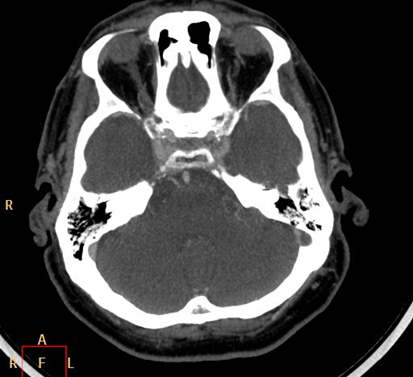

Although, subarachnoid hemorrhage (SAH) is most often caused by the rupture of a berry aneurysm, arteriovenous malformation (AVM) and trauma can also lead to it. SAH is typically located at the basal subarachnoid spaces, which then propagates along the lateral fissures or it fills up the interhemispheric fissure till the convexities. The main collection of the blood is usually indicative of the source of origin. In cases of parenchymal spread the mechanism, whether it broke in, or it broke out from the parenchyma could represent a differential diagnostic challenge. When accompanied by brain edema, the consequent herniation can result in parenchymal infarcts as well.

CT angiography examination is usually advisory in order to confirm the site of the bleeding. It is also effective when a hemorrhagic tumor is in the differentials, although complete differentiation might only be achieved by follow-up examinations. CTA is also essential in the diagnostics of multiple aneurysms (which are prevalent in 20-30% of the cases based on autopsy reports.) In case of a subarachnoid hemorrhage the consequently developing hydrocephalus and its degree might only be detected on follow-up CT examinations. It is very important to note that an initial brain aneurysm rupture might be followed by a second one within the first 7 – 10 days and the resulting vasospasm carries a much higher risk of mortality than the one at the time of the first SAH. This is why the scrutonius review of the acute diagnostic imaging is essential and it plays a fundamental role in patient treatment. Open brain surgery of the aneurysm (clipping) has been replaced by catheter angiography (DSA) nowadays. The aneurysm is either filled up with thrombogenic coils through its neck or recently bypassing stents are inserted to exclude the aneurysm from the cerebral circulation.